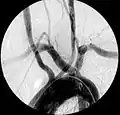

Artère sous-clavière droite aberrante à l'angiographie.